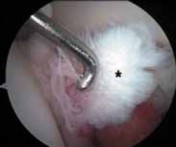

*

TECHNIQUES

LABRAL DÉBRIDEMENT

1. Most symptomatic labral tears are managed with selective débridement of the damaged portion ( TECH FIG 1).

2.

Emphasis is given to preserving healthy tissue, because removal of normal labrum can lead to poorer results.

3.

A complete joint survey is performed with thorough inspection and palpation of the labrum, identifying its damaged portion.

4.

Most labral resection is carried out with a power shaver, debulking the damaged tissue.

1.

Hand instruments and an arthroscopic knife may aid in this resection.

It is important to preserve the healthy tissue but create a stable transition zone when completing the débridement.

A radiofrequency device is especially useful for this because of the limited maneuverability imposed by the architecture of the joint.

Diseased tissue has an increased water content and responds selectively to the thermal device.

TECHNIQUES A B TECH FIG 1 • Arthroscopic view of a right hip from the anterior portal. A. A fragmented labral tear with degeneration within its substance is identified. B. Débridement is initiated with the power shaver. C. A portion of the comminuted labral tear is conservatively stabilized with a radiofrequency probe. D. The damaged portion has been removed, preserving the healthy substance of the C D labrum. LABRAL REPAIR